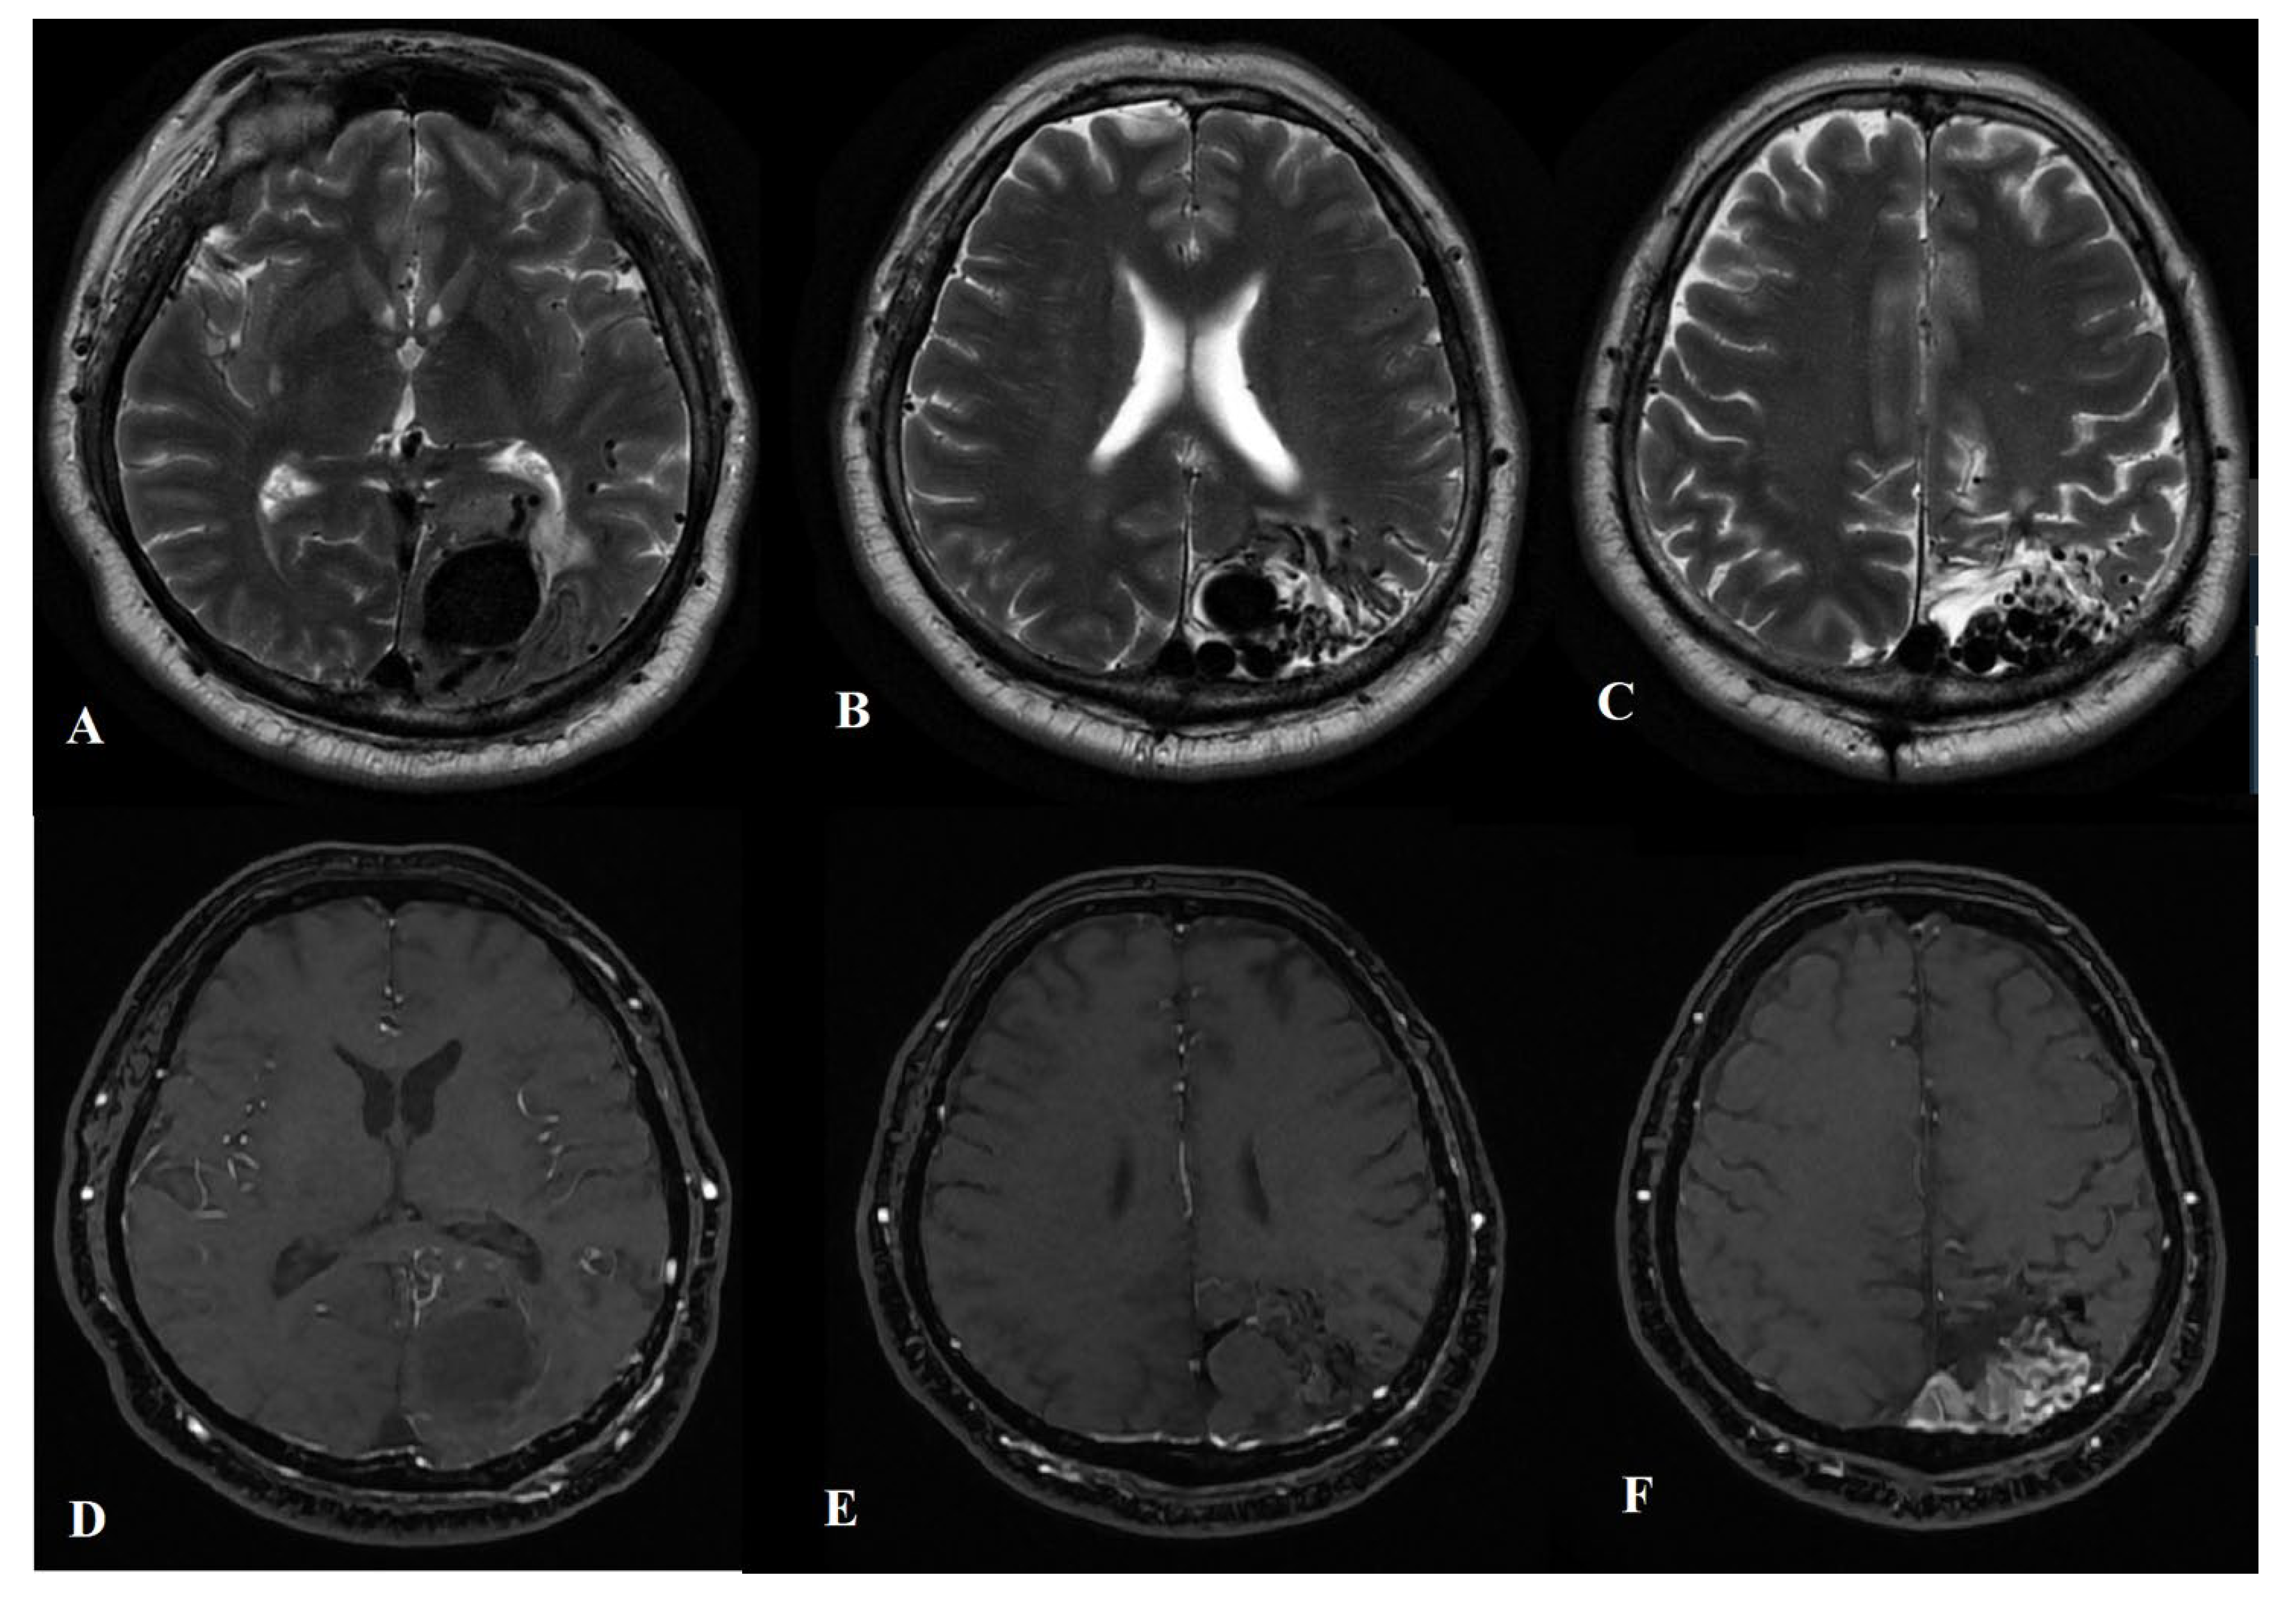

2.1. Diagnostic Procedures